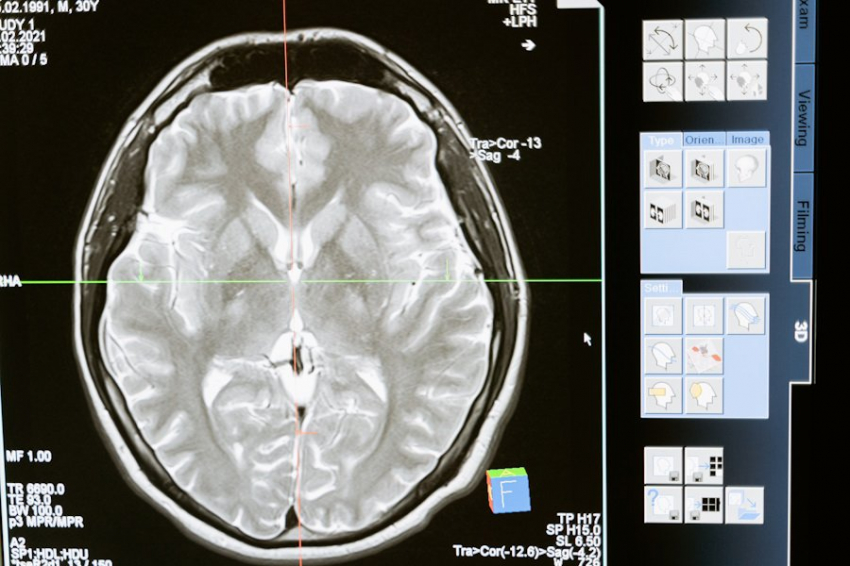

Фото из открытых источников

Учёные из различных стран, включая специалистов из Duke-NUS, раскрыли секрет активации "спящих" нейронных стволовых клеток в мозге. Это открытие имеет огромное значение для понимания процессов восстановления и регенерации нервной ткани.